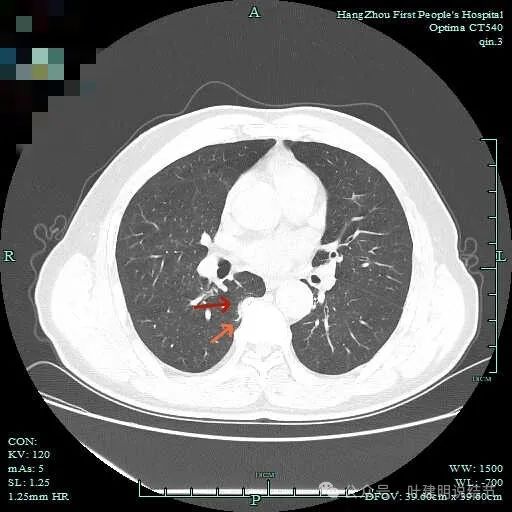

与脊柱间似乎有间隙在,另见微小血管进入这条索状的偏高密度影处。

有细小血管进入,但说不上异常增粗。病灶仍是小片状,条状。

磨玻璃成分密度淡且界欠清,整体就是条索状弯曲的。

上图见细毛刺明显。

病灶实性伴细毛刺,与脊柱间有间隙在。